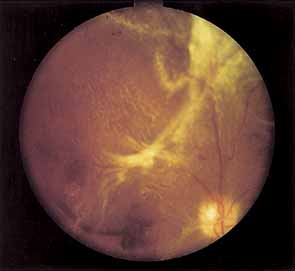

Once the stimulus for growth of new vessels is present the vessels grow along the path of least resistance. The absence of the internal limiting membrane over the optic disc could explain the proclivity of new vessel growth at that location. Neovascularization grows readily along connective tissue scaffolding such as the posterior hyaloidal face (Fig. 11).

The new vessels, initially naked, usually progress through a stage of further proliferation with associated connective tissue formation. As PDR progresses, the fibrous component becomes more prominent. Fibrotic tissue can be vascular or avascular. The fibrovascular variety is usually found in association with vessels extending into the vitreous cavity or with abnormal new vessels on the surface of the retina or disc. The avascular variety usually results from organization or thickening of the posterior hyaloid face.

Posterior vitreous detachment in diabetics is characterized by a slow, overall shrinkage of the entire formed vitreous rather than by the formation of cavities caused by vitreous destruction.14 Davis15 has stressed the role of the contracting vitreous in the production of vitreous hemorrhage, retinal breaks, and retinal detachment. Neovascular vessels do not “grow” forward into the vitreous cavity; they are pulled into it by the contracting vitreous to which they are adherent (see Fig. 11). Vitrectomized eyes rarely develop new areas of neovascularization and existent neovascularization tends to regress. If severe enough, posterior vitreous detachment may result in retinoschisis, retinal detachment, and retinal break formation. In eyes fortunate enough not to develop these complications, the neovascularization may burn out, leading to atrophy of the new vessels.